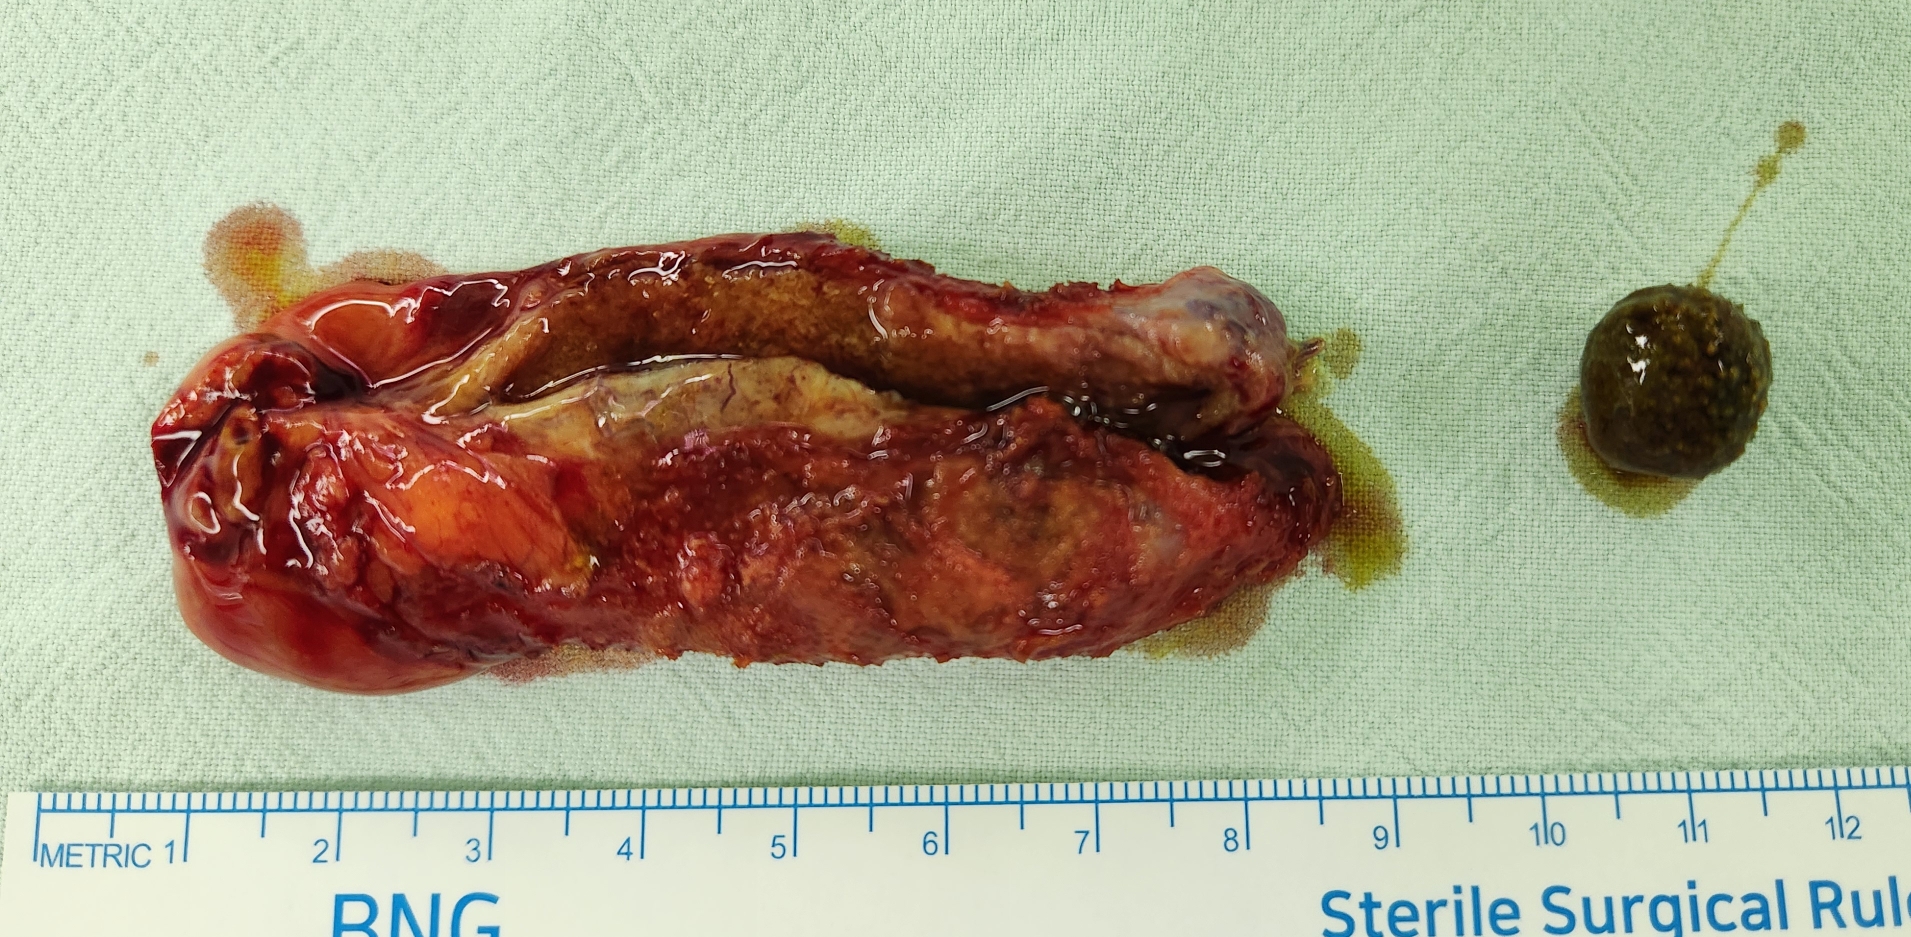

상복부통증으로 한일의원에서 초음파 시행후 담석 담낭염으로 수술 위해 제 외래로 오셨던 분입니다.

방금 단일공 복강경 담낭절제술을 시행했습니다.

수술은 15분 걸렸습니다.